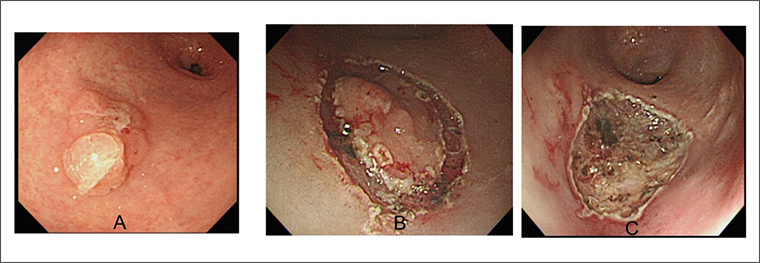

▲橡皮筋輔助黏膜切除術執行過程。(圖/安南醫院提供)

許秉毅說明,橡皮筋輔助黏膜切除術是透過內視鏡微創技術,利用「橡皮筋」結紮於息肉的底部,將「寬大息肉」迅速整形成「圓球狀息肉」,這樣圈套型電燒刀便可輕易套住息肉底部,進行完整之息肉切割,並避免胃被燒破。